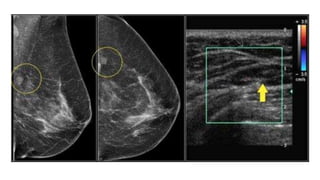

• #59 MAMMOGRAM SHOWED A 1.5CM MASS AND USG WAS ADVICED WHICH SHOWED A PARELLEL SOILD WELL CIRCUMSCRIBED MASS THAT IS PROBABLY BENIGN